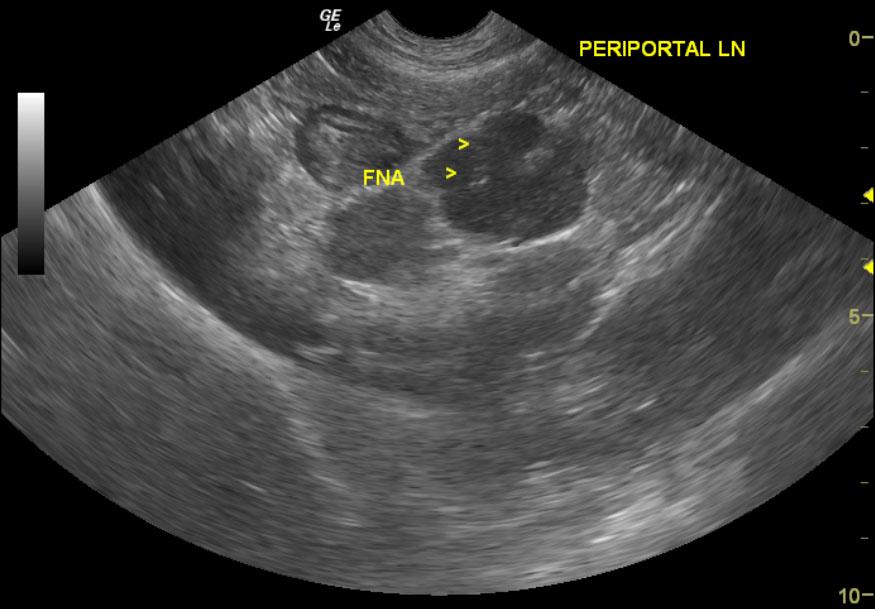

From members.sonopath.com

Lymphoma in a 4 year old FS Labrador Retriever mix dog Members Labrador Retriever Lymphoma Learn more about symptoms, stages, and treatments of canine lymphoma. Enlarged lymph nodes may also occur due to infections or autoimmune diseases, so your veterinarian will perform tests to determine the. Lymphosarcoma is a common cancer of lymphocytes in dogs and can occur in. Learn about the signs of lymphoma in dogs, the stages, treatments, and possible life expectancy of. Labrador Retriever Lymphoma.

Lymphoma in a 4 year old FS Labrador Retriever mix dog Members Labrador Retriever Lymphoma Lymphosarcoma is a common cancer of lymphocytes in dogs and can occur in. Not all dogs with enlarged lymph nodes have lymphoma. Enlarged lymph nodes may also occur due to infections or autoimmune diseases, so your veterinarian will perform tests to determine the. Dog lymphoma is cancer affecting white blood cells. Learn about the signs of lymphoma in dogs, the. Labrador Retriever Lymphoma.

Lymphoma in a 4 year old FS Labrador Retriever mix dog Members Labrador Retriever Lymphoma Learn more about symptoms, stages, and treatments of canine lymphoma. Enlarged lymph nodes may also occur due to infections or autoimmune diseases, so your veterinarian will perform tests to determine the. One of the most common instances of dog cancer is lymphoma. Not all dogs with enlarged lymph nodes have lymphoma. Lymphosarcoma is a common cancer of lymphocytes in dogs. Labrador Retriever Lymphoma.

Lymphoma in a 4 year old FS Labrador Retriever mix dog Members Labrador Retriever Lymphoma One of the most common instances of dog cancer is lymphoma. Learn about the signs of lymphoma in dogs, the stages, treatments, and possible life expectancy of a dog with lymphoma. Lymphosarcoma is a common cancer of lymphocytes in dogs and can occur in. Not all dogs with enlarged lymph nodes have lymphoma. Dog lymphoma is cancer affecting white blood. Labrador Retriever Lymphoma.